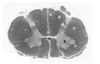

Which pathway runs through the region indicated by the asterisk?

- Lateral lemniscus

- Spinothalamic tract

- Vestibulospinal tract

- Corticospinal tractt

- Spinocerebellar tract

Which pathway runs through the region indicated by the asterisk?

- Lateral lemniscus

- Spinothalamic tract

- Vestibulospinal tract

* *4. Corticospinal tractt** - Spinocerebellar tract